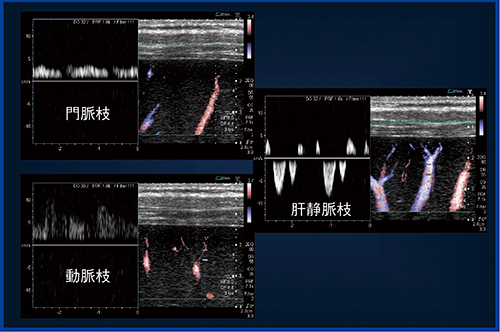

SMIは,末梢血管のFFT解析においても有用である。

以前,当院でカラードプラを用いて,肝臓表面から深さ1cmの血管についてFFT解析による検討を行った。末梢に向かう血流にカーソルを置いて解析すると,血流パターンが波形で表示され,Pパターン(門脈のみ),APパターン(門脈と動脈),Aパターン(動脈のみ)を判別することができる。肝硬変(18例),慢性肝炎(19例),正常例(9例)で血流パターンを比較したところ,肝硬変ではAパターンが多く,正常例ではPパターンが多い結果となった。

このように,FFT解析により,末梢に向かう血流の門脈と動脈のバランスの変化を知ることができるが,カラードプラでFFT解析をするには,ROIの設定で画像を安定させるために長時間の息止めが必要であるなど,実施は容易ではなかった。ところがSMIを用いると,非造影でも末梢血管が明瞭に描出されるためROIを設定しやすく,短時間の息止めですむなど,施行者,患者双方の負担を軽減しつつ,簡単にFFT解析を行うことができる(図8)。

図8 SMIを用いた肝臓表面近傍血管のFFT解析結果